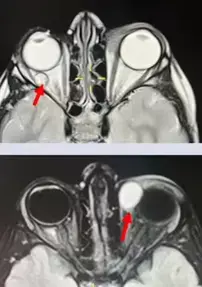

Рисунок 19. КТ и МРТ подтверждают объемные образования правой и левой орбиты.КТ и МРТ подтверждают объемные образования правой и левой орбиты (см. рис. 19).

На МРТ видно, что новообразование состоит из двух частей, одна из которых кистовидная, а другая гипоэхогенна по отношению к мозговой ткани. Образование вызывает компрессию мышц глаза, смещает зрительный нерв.

— На МРТ мы видим образование, которое находится под верхней стенкой глазницы, тесно примыкает к глазному яблоку и мышцам (см. рис. 10). Проводим трансконъюнктивальную орбитотомию и выделяем образование, тесно связанное с верхней косой мышцей (см. рис. 11). К сожалению, ее при выделении образования приходится пересечь. Иммуногистохимическое исследование подтверждает эмбриональную рабдомиосаркому, — рассказывает офтальмохирург. — Пациент продолжил лечение у онкологов. На данный момент он в ремиссии уже 3 года. Мы прооперировали его по поводу вертикального непостоянного косоглазия, которое развилось вследствие того, что мы резицировали часть верхней косой мышцы.